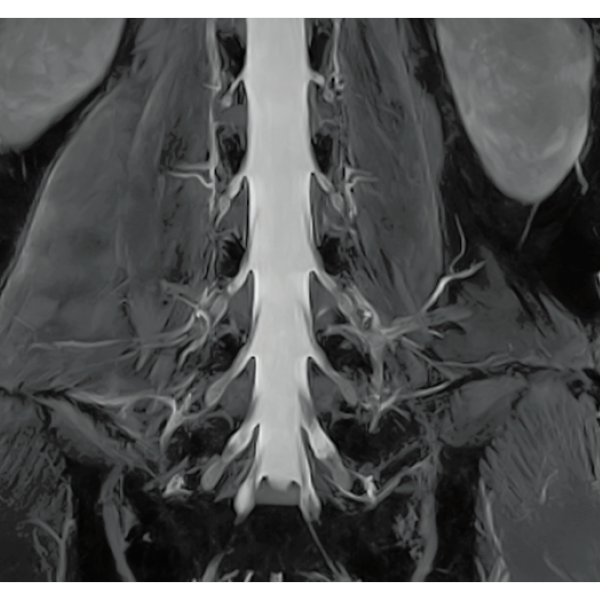

IP-RAPID×DLR PlusはVolumeScanやRadialScan、HalfScanといった基本撮像に加え、MultiContrastScanのFatSepやDWIなど多くの撮像法でお使いいただけます。広範囲DWIやWhole Spine撮像など時間のかかるWide Scanにも併用でき、多くの部位で従来よりも詳細な情報を得ることができます。

2DFSE

3DGrE Bone Imaging

3DPBSG

2DGrE

2DBASG